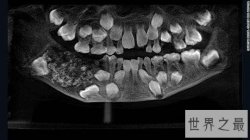

一名七岁的印度男孩在爸爸妈妈的陪同下前往金奈南部的牙科医学院。据报道,他自三岁起就向爸爸妈妈抱怨过下巴肿胀不适,当时爸爸妈妈曾带他去过另一家医院。但由于年岁太小,...